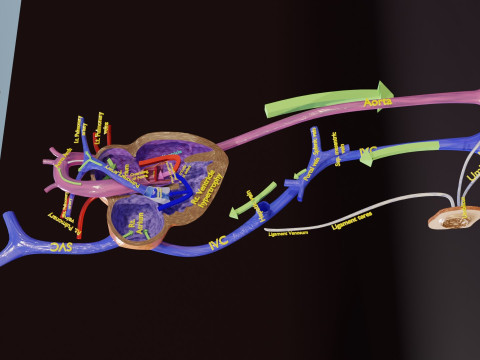

The model meshes include adult circulation versus circulation in Tetralogy of Fallot (TAF), arrow labels and text labels. The blood flow in a patient with Tetralogy of Fallot is outlined in this model. To contrast it to normal blood circulation a separate model of normal circulation is included. The Tetralogy of Fallot (OVER RIDING OF AORTA, PUL STENOSIS, VENTRICULAR SEPTAL DEFECT, RIGHT VENTRICULAR HYPERTROPHY), fossa, ligament teres , venosus, and arteriosus are duly depicted with proper labelling and blood flow directional arrows. Excellent model for teaching, demonstration and knowlegde of human body. The models include both procedural and image textures blend files separately. The texture file include diffuse, roughness and normal png and jpeg based on non overlapping UV maps.